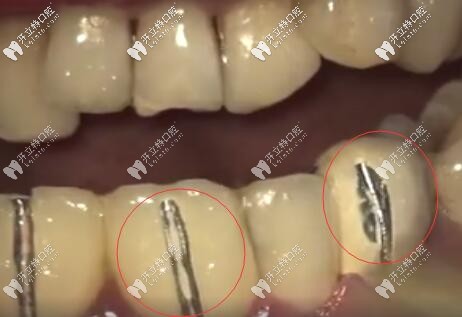

烤瓷牙牙齦黑線

因?yàn)槌霈F(xiàn)牙齦黑線也說明烤瓷牙牙冠與牙根之間不密合,已經(jīng)有一條縫了,有了這條縫,食物殘渣、細(xì)菌等都容易從這條縫進(jìn)入牙套里去。